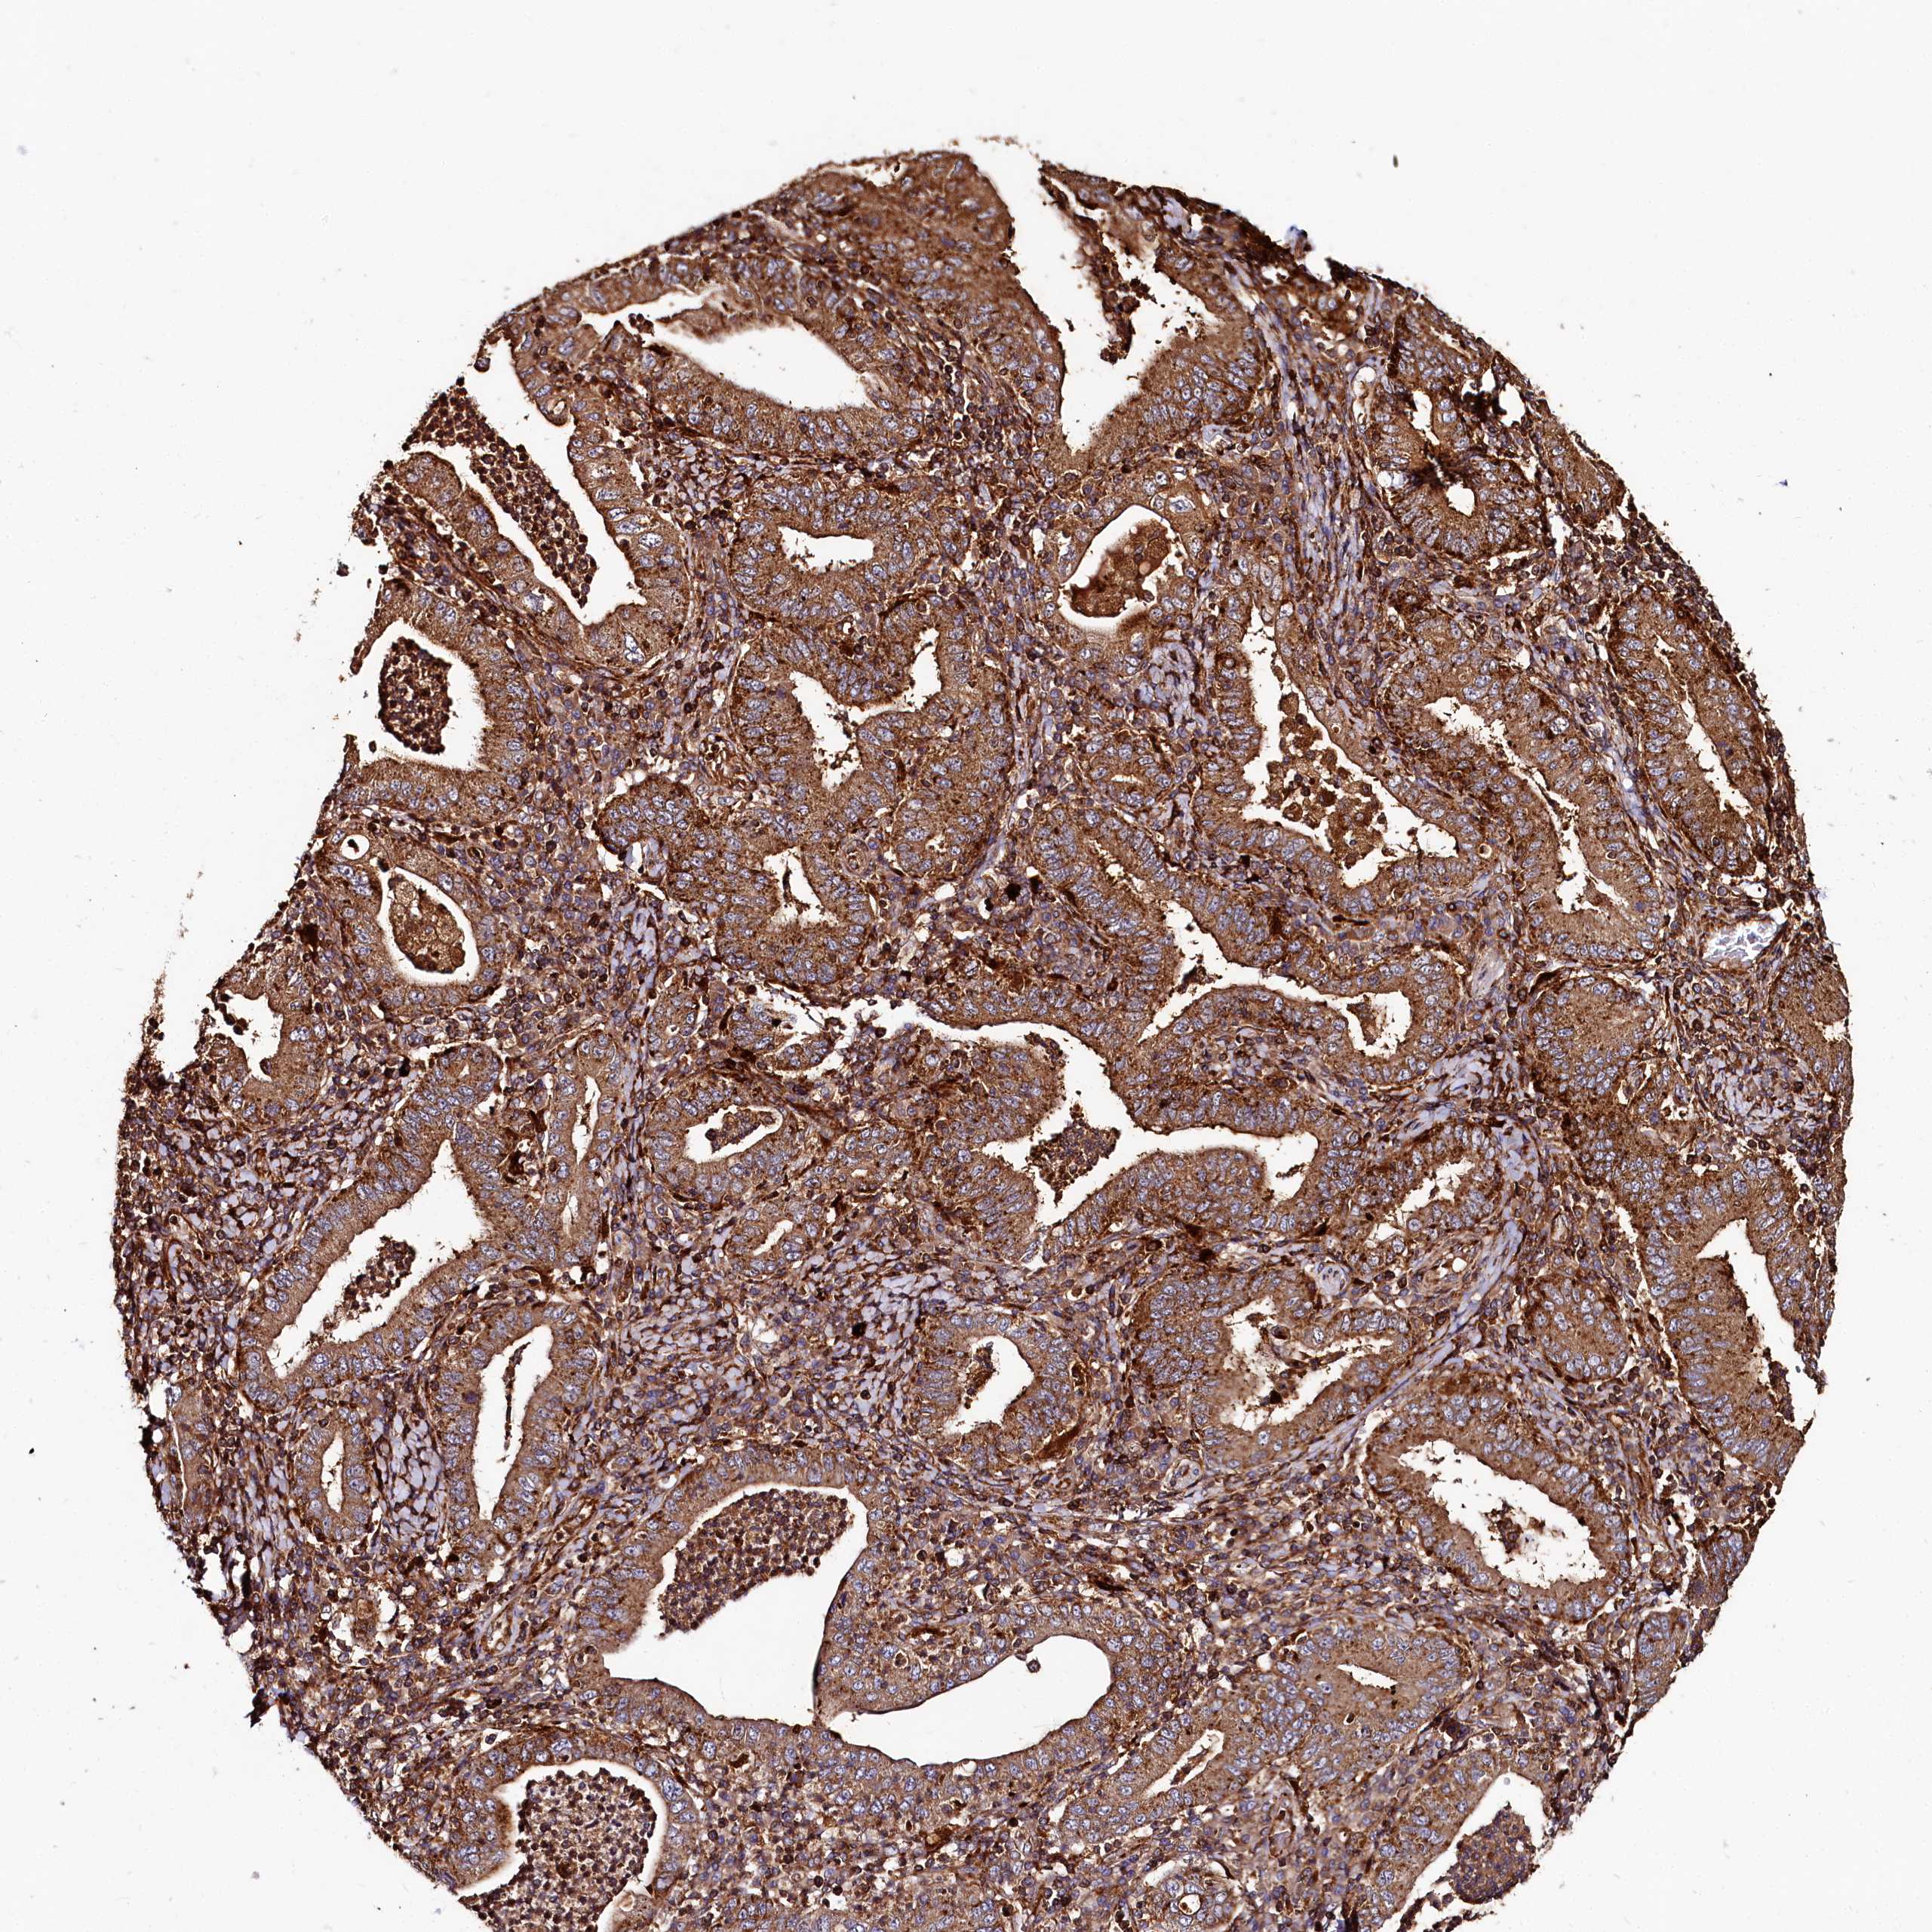

STOMACH CANCER - Protein expressioni

A mouse-over function shows sample information and annotation data. Click on an image to view it in a full screen mode. Samples can be filtered based on level of antibody staining by selecting one or several of the following categories: high, medium, low and not detected. The assay and annotation is described here.

Antibody stainingi

Antibody staining in the annotated cell types in the current human tissue is reported as not detected, low, medium, or high, based on conventional immunohistochemistry profiling in selected tissues. This score is based on the combination of the staining intensity and fraction of stained cells.

Each image is clickable and will lead to virtual microscopy that enables deeper exploration of all samples and also displays staining intensity scores, fraction scores and subcellular localization as well as patient and tissue information for each sample.

Antibody HPA039357

Staining

High

Medium

Low

Not detected

Intensity

Strong

Moderate

Weak

Negative

Quantity

>75%

75%-25%

<25%

None

Location

Nuclear

Cytoplasmic/membranous

Cytoplasmic/membranous,nuclear

Adenocarcinoma, NOS

Adenocarcinoma, High grade